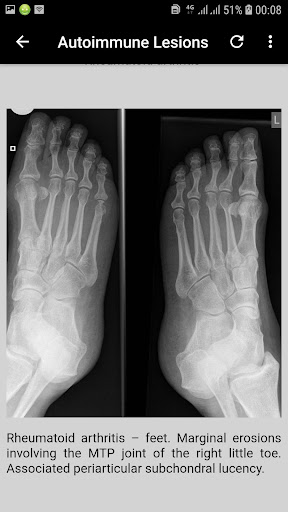

In the context of trauma at least 2 views of the body part in question are usually required. If looking for specific disease entities, for example erosions in rheumatoid arthritis, this may be less important. In some cases, such as possible scaphoid injury, more than 2 images are required.2 views are better than 1